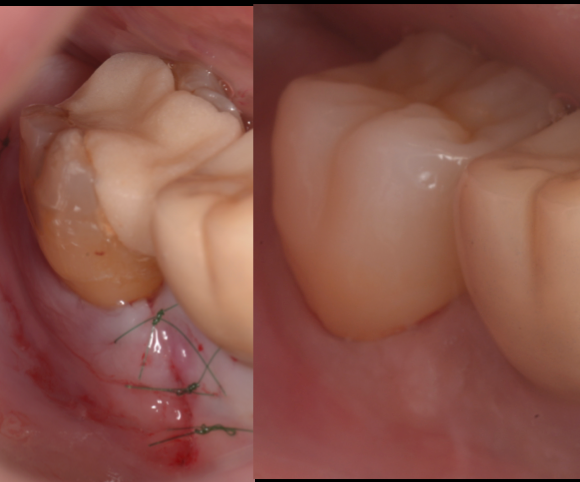

治療前

治療後

池袋院での症例紹介

グランドメゾンデンタルクリニックでは、歯周病専門医がマイクロスコープと歯科用CTを駆使し、根分岐部病変への適切な診断・治療を行っています。

- 抜歯回避のための「ルートセパレーション+補綴設計」

通常では見えない部位の歯石・感染源を徹底除去します。 - 骨再生療法(GTR法・エムドゲインなど)

歯槽骨の再建を図り、機能の回復をめざします。 - 定期的なSPT(サポーティブ・ペリオ・テラピー)